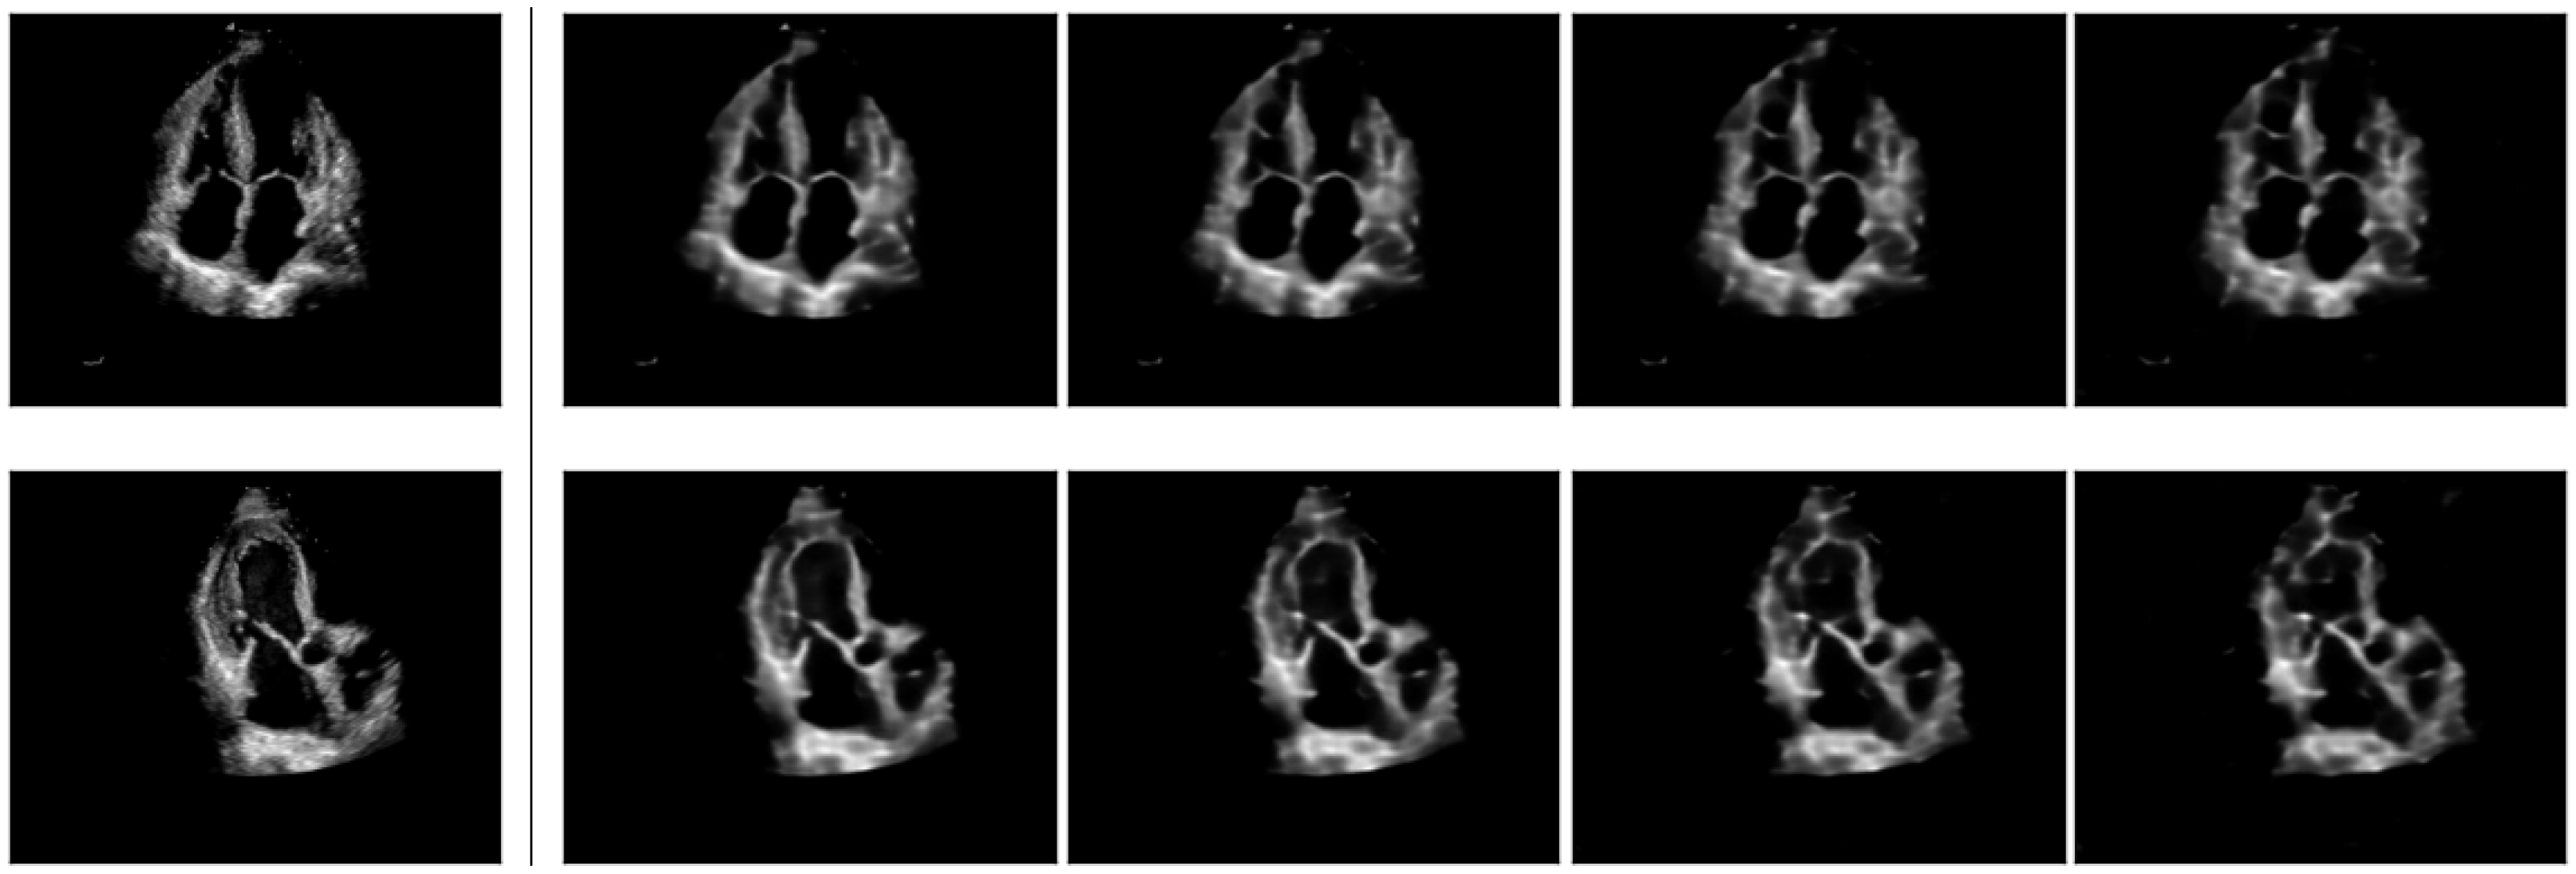

Upon convergence, the pre-trained model can be qualitatively analysed by examining the inferred concept probability maps for test images. A straightforward method to implement this involves selecting the most likely concept at each grid location () and overlaying the up-sampled concept indices grid onto the initial input images, as in Figure 3. The probability of the most likely concept at each location can be incorporated in the visualisations.

Figure 3.

Concept maps for three randomly sampled inputs. The 16×-stride concept grid is up-sampled to the original image size. The indices of the most likely concept for each grid location are displayed in red at the bottom-left of each location. The grid is color-coded according to concept indices for better visualisation.

By examining a random selection of samples illustrated in Figure 3, we can make the following initial observations:

- The prior constraint, which requires regions outside the cone to be modeled solely by the first concept (i.e., the background concept at index 0) is generally respected. Exceptions occur at grid locations in the cone’s proximity, particularly at the boundaries between the cone and the background. As these are transition regions, they are not particularly concerning, since the model’s confidence is expected to be low for such regions.

- Certain concepts are specialized for specific anatomical structures. For example, concept models blood pools within the cone, concept represents the Left Ventricle (LV) free wall on the right hand size of the cone, concepts and correspond to septum walls, and concept covers the right-heart side of the cone, among others.

- Certain concepts, such as e.g., and appear more isolated and spanning a single grid location. By qualitatively assessing multiple input samples, we hypothesise these concepts encode information about the local anatomical shapes of nearby larger concept islands. It appears these concepts have larger confidence assigned to them than the average confidence inside larger concept islands. We term them modifier concepts.